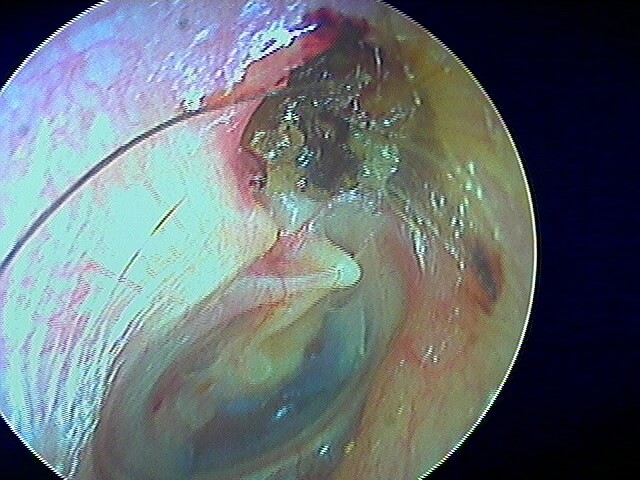

2/5 otite externe mycotique ou otomycose

Dans ma pratique, je vois plus d'otomycose à Aspergillus niger, très caractéristique avec ces points noirs.

La même oreille après aspiration: